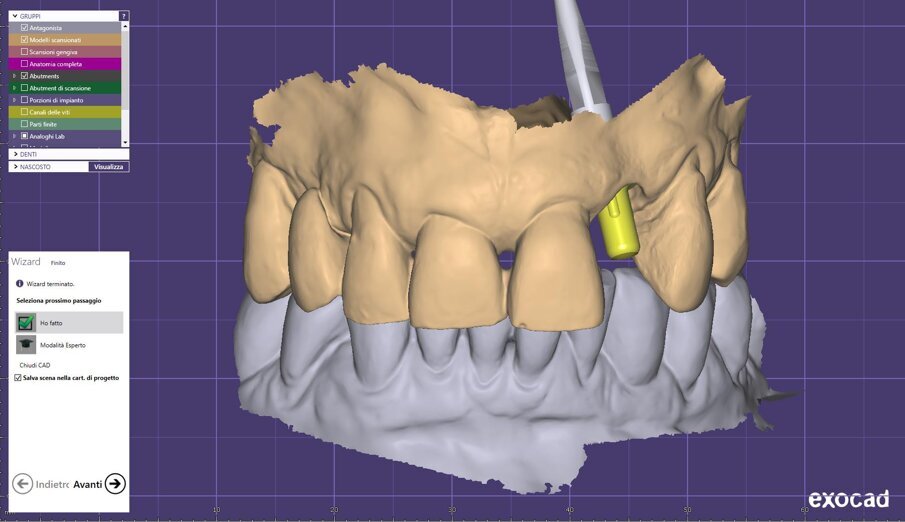

A 7 giorni è stato eseguito un controllo per verificare lo stato dei tessuti gengivali e continuare a motivare la paziente riguardo all’esclusione dai carichi masticatori (Fig. 9). A 90 giorni è stato rimosso il provvisorio per procedere al restauro ceramico. Nonostante la superficie SLActive preveda un accorciamento dei tempi di integrazione, è stato deciso un tempo di attesa convenzionale per accertarsi della stabilità dei tessuti molli perimplantari (Figg. 10-12). È stato eseguito un workflow digitale a partire dall’impronta ottica, fino alla realizzazione di un restauro in Zirconia precolorata e stratificata vestibolare (Dental Direkt 1200 e Creation ZI-CT) su base titanio (Figg. 13, 14). Il restauro è stato consegnato mediante avvitamento a controllo di torque secondo le indicazioni della casa produttrice (Figg. 15, 16).

Fig. 13_Workflow digitale per la realizzazione della corona.

Fig. 14_Passaggi digitali di laboratorio.